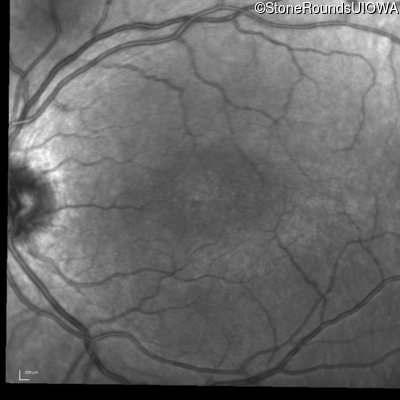

Infrared Fundus Photograph - Right - 20/63 -2

Exemplar

Infrared Fundus Photograph - Left - 20/50